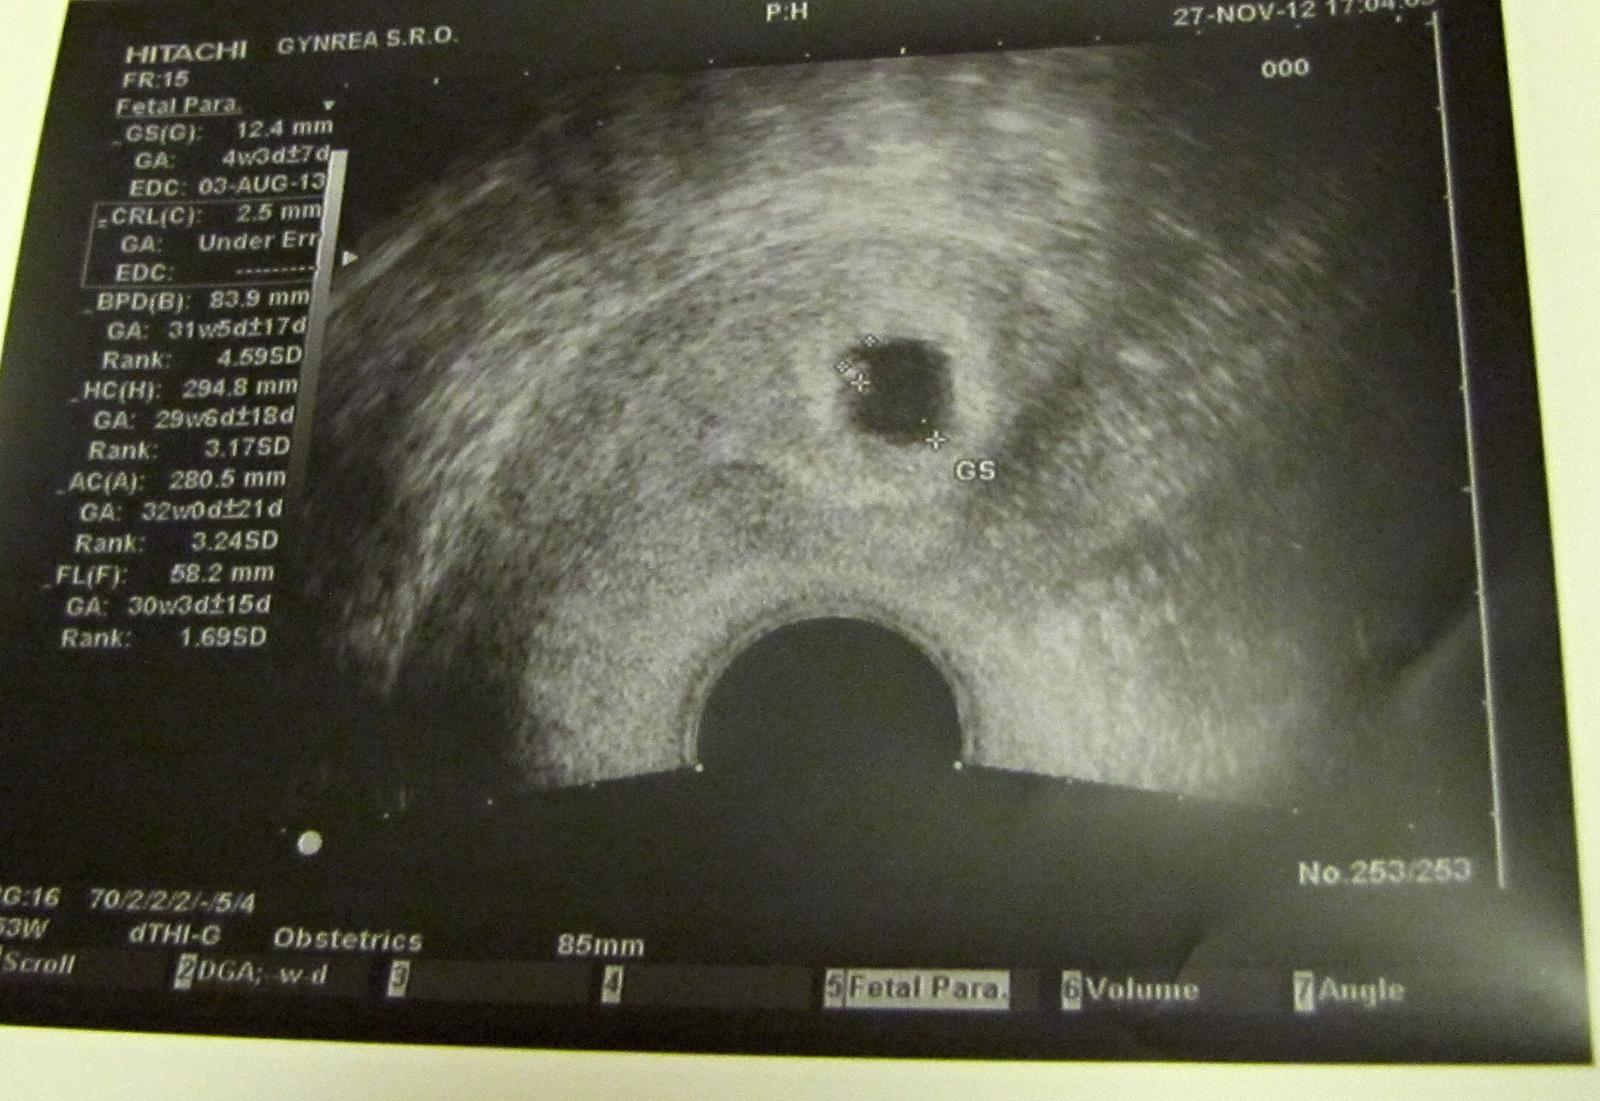

podla teploty ovulacia prebehla cca 14,15 dc.. uz si hore, bud si 1 alebo 2 dpo, kedze si nemerala ten jeden den, cize tentokrat to sedi s ultrazvukom.